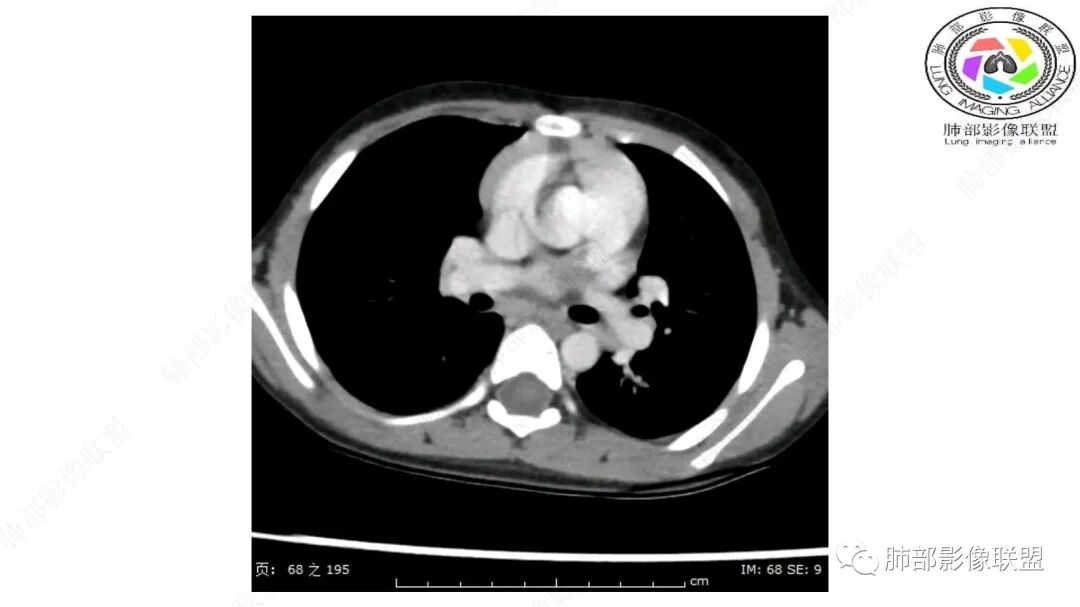

定位:肺内?尖段气管未见明显显示,腔静脉受压向右推移?病灶内可见前段动脉穿行,脂肪密度为主。

肿块起源于右上气管分叉处?强化动脉血管最后汇入右肺动脉上干。

右侧纵隔奇静脉水平起源?压迫上肺,包绕动脉?

第一个问题:定位:肺内?纵隔?

病灶属于交界区,主体位于肺内,占位效应明显,前方突入胸壁,胸腺受压变形,胸膜显示欠清楚;病灶包绕上叶肺动脉;似乎有体动脉供血。符合肺内的点:包绕上叶肺动脉分支;符合纵隔的点:前方似乎突入胸壁,与胸腺关系比较密切,但是与上腔静脉的关系提示病灶不支持纵隔来源,前纵隔的常规会将上腔静脉受压后移、外移,这是不符合的。

从这个角度符合肺内的,有一点不太踏实的是:似乎突入前胸壁。

2.肺动脉穿行也许是肺内来源最重要支持点!